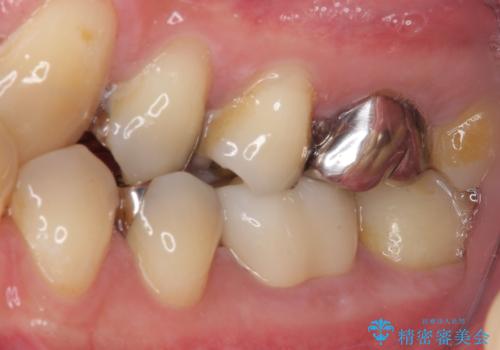

- 保険診療で装着した奥歯の白いクラウンの具合がよくないとのことで来院された患者様です。

保険診療で安価に白いクラウンが入れられるということで選択されたそうですが、装着後に痛みを感じたり、ものが挟まって不快であったりと不便が多いため、セラミッククラウンにて補綴治療を行うこととしました。

保険診療では、安価に白いクラウンを装着できる代償として、歯とクラウンの境目が不適合であったり、歯と歯の間にものが挟まりやすかったりと、不快な思いをされることがしばしばあります。

自費診療は、費用が高くなりますが、よい材料を選択したり、診療時間を十分にとったりできるため、単純に白いだけではない、良質なクラウンを装着することが可能です。